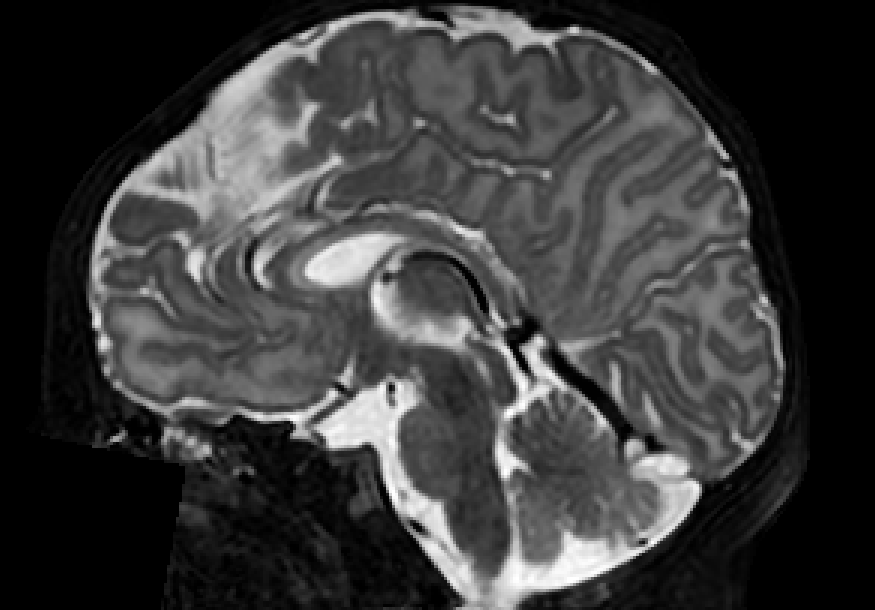

The dataset consisted of 70 3D T2-weighted brain MRI scans publicly available from the dHCP neonatal cohort. The segmentation maps had 10 classes, corresponding to: zero-pixel background, cerebrospinal fluid (CSF), cortical grey matter (cGM), white matter (WM), background bordering brain tissues, ventricles, cerebellum, deep grey matter (dGM), brainstem, and hippocampus. The scans covered an age range of 24.3-42.2 weeks. The data was available in NIfTI format; Figure 1 shows an example scan and corresponding tissue labels. We carried out a pre-processing step where each scan was independently normalised to zero-mean and unit-variance.